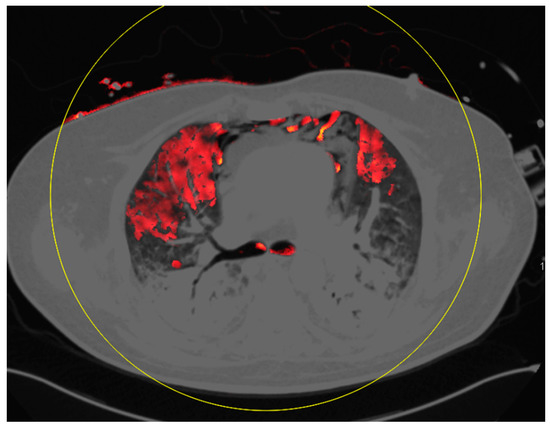

Dual-Energy Computed Tomography of the Lung in COVID-19 Patients: Mismatch of Perfusion Defects and Pulmonary Opacities